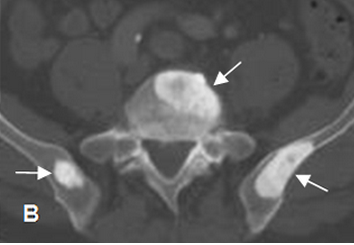

Patrones de las metástasis óseas. A Cáncer de pulmón ... 😈

FENOTIPO METASTÁSICO EN EL CÁNCER DE PRÓSTATA, UROLOGÍA 😈